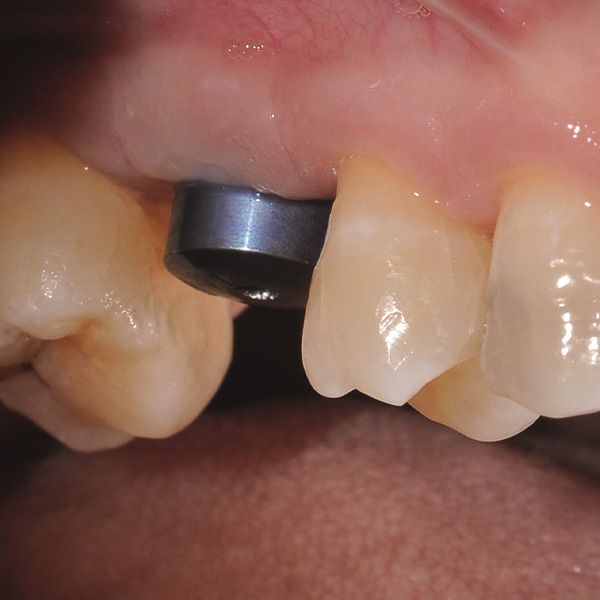

Implantatgetragene Kronenrekonstruktion aus der Hybridkeramik VITA ENAMIC mulitColor

Restaurationen auf Implantaten sind besonders hohen Belastungen ausgesetzt. Da dem Patienten der elastische Faserapparat des natürlichen Zahnbetts fehlt, werden Kaukräfte nicht absorbiert, sondern direkt auf die Restauration, das Implantat, den Knochen sowie die Gegenbezahnung übertragen. Die Hybridkeramik VITA ENAMIC verfügt über eine duale Netzwerkstruktur aus Keramik und Polymer. Daraus resultieren eine dentinähnliche Elastizität und die Fähigkeit, Kaukräfte zu absorbieren. Der mehrfarbige Rohling VITA ENAMIC multiColor in der Geometrie EMC-16 ermöglicht aufgrund seiner hohen vertikalen Dimension auch bei atrophiertem Knochen die Herstellung einteiliger, monolithischer Abutmentkronen. Zahnarzt Professor Dr. Alexander Hassel zeigt im folgenden Beitrag, wie er eine Patientin mit dieser Restaurationsform versorgt.